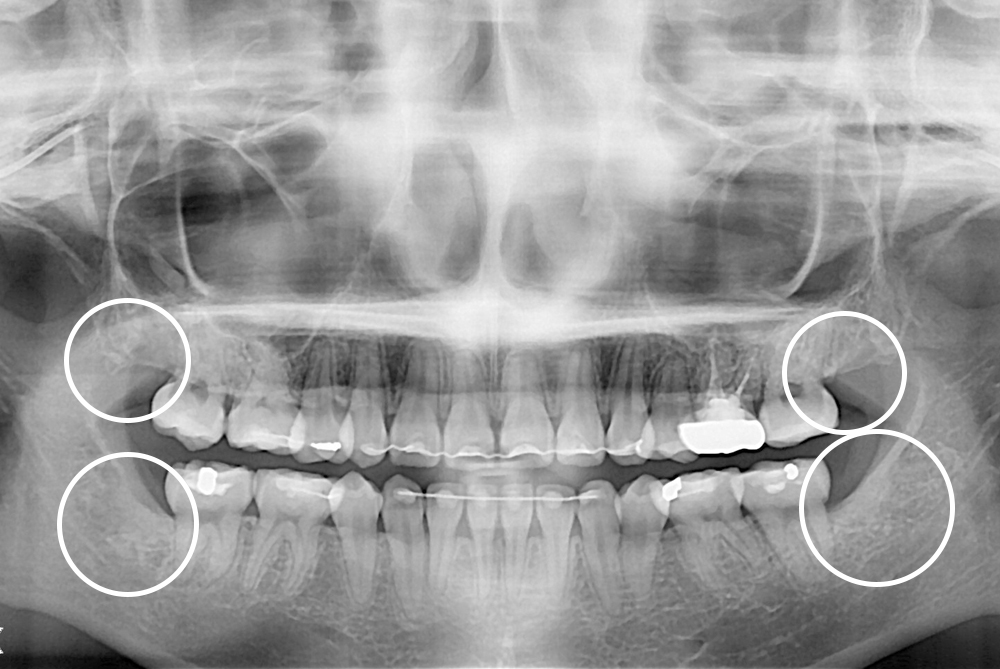

치료후 : 2019-08-05

세종치과는 구강악안면외과학 박사이신 원장님이 발치하는 치과입니다.